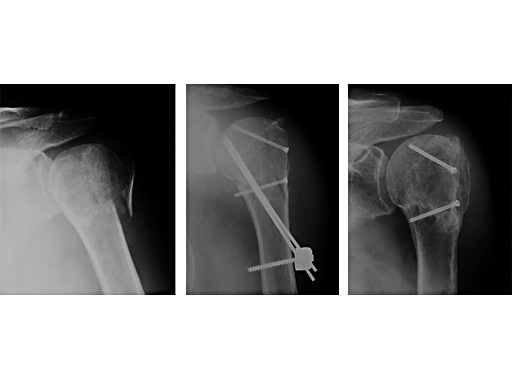

62 year old female patient

Fig 1

Accident

Fig 2

postoperative

Fig 3

Fracture healed